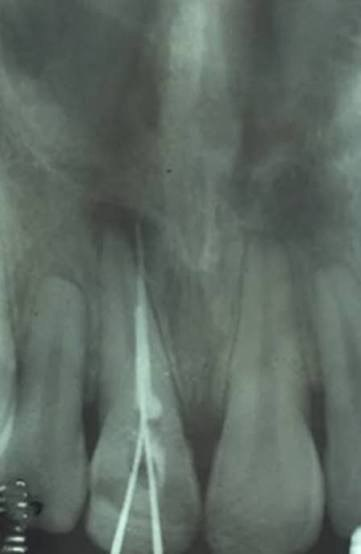

4. What type of perforation is being treated by an endodontist in this X ray?